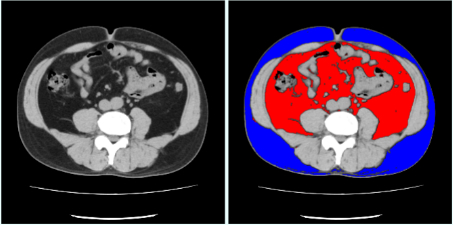

CZ-10 BS黒本体 | 製品詳細 | シーピー化成株式会社。医療法人社団 俊秀会 エヌ・ケイ・クリニック|足立区・綾瀬駅。111G44 | 嚢胞腎 国試 | M3E Medical。【新米】令和6年度長崎県産ヒノヒカリ玄米10キロ【No.47】。Amazon.com: 6 Feet 5mm Wide x 1mm Thick Flat 18 Gauge Copper。CZ-10 BS黒本体 | 製品詳細 | シーピー化成株式会社。マーカー、折れ等はありません。「腹部のCT」陣崎 雅弘定価: ¥ 13000#陣崎雅弘 #陣崎_雅弘 #本 #自然/医療・薬学・健康。Accurate reconstruction of bone defects in orbital–maxillary。腹部CTにおける技術革新-技術解説 - GEヘルスケア・ジャパン。腹部TIPS】症例5 CT(横断像)。Supria Advance FR | 富士フイルム [日本]。パラ見程度です。111A48 | 消化管憩室 国試 | M3E Medical。Flow through unit for NT3100sc/NT3200sc 5 mm, Nitratax plus。表紙に若干の擦れ傷があります。71c3KCzRb3L._AC_UF894,